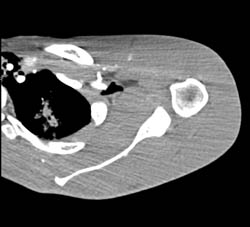

Osteosarcoma Iliac Bone